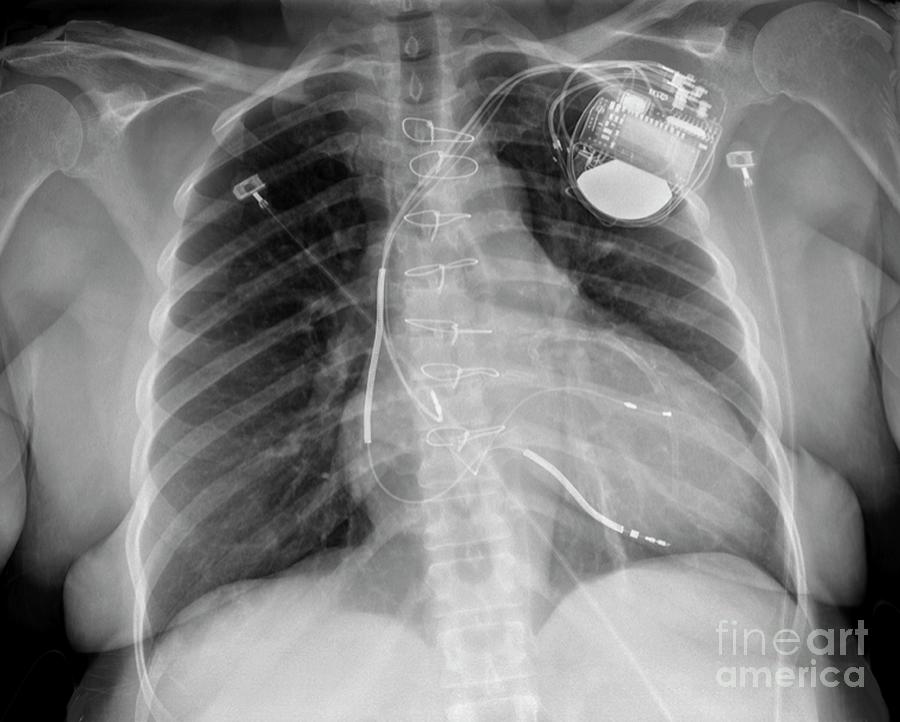

From pixels.com

Pacemaker In Heart Disease Photograph by Dr P. Marazzi Will A Pacemaker Help With Heart Failure An icd does not improve heart function or relieve symptoms of advanced heart failure. However, an icd works as a key. This happens when your heart. A pacemaker monitors your heart rate and sends small and painless electrical impulses to the right ventricle of your heart to start each heartbeat. The pacemaker can regulate your heartbeat. Doctors have been puzzled. Will A Pacemaker Help With Heart Failure.